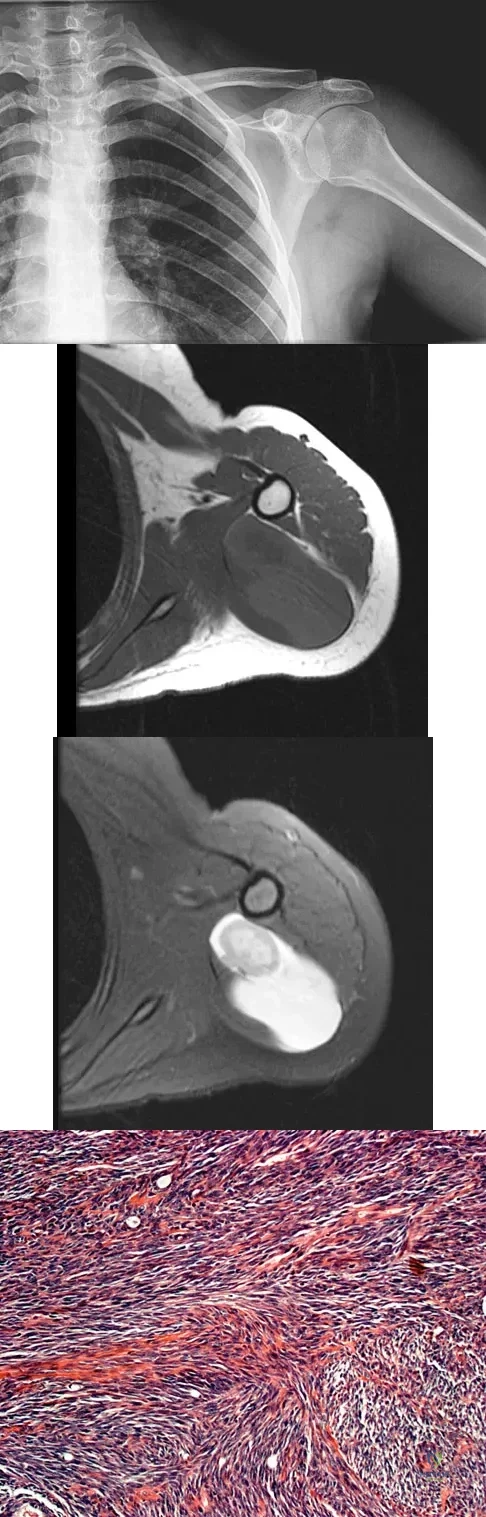

Question 16

A 16-year-old girl has had painless swelling in her posterior left arm for the past 4 months. A radiograph, MRI scans, and an incisional biopsy specimen are shown in Figures 43a through 43d. What is the cytogenetic translocation most commonly associated with this tumor?

Explanation